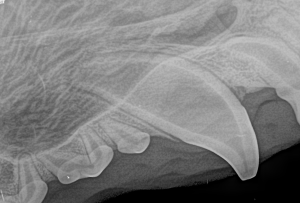

Feline Full Mouth Radiograph example